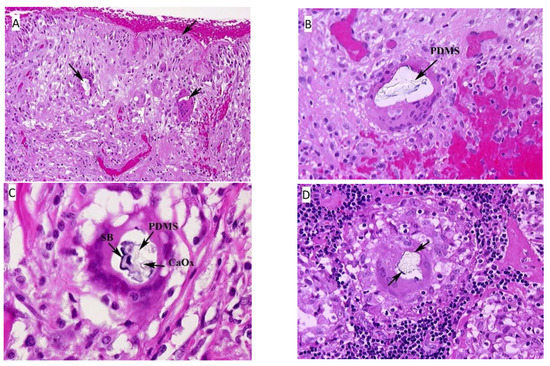

3.1. Histology

3.1.1. Capsule Surrounding the Implant, Bilateral

3.1.2. Axillary Lymph Node, Left

3.1.3. Eyelid Nodule

3.1.4. Leg Nodule